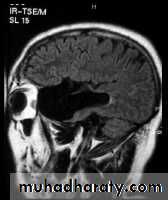

ARNOLD CHIARI MALFORMATION

1-Donward herniation of cerebellar tonsil & medulla oblongata beneath level of foramen magnum.

2- elongation of 4th ventricle.

3- associated with aqueduct stenosis.

4- associated with myelomeningocele.